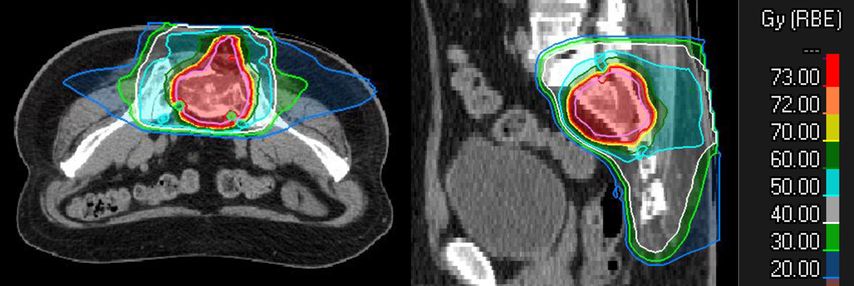

MedAustron behandelt nationale und internationale Patient*innen. Eine Therapieanfrage kann durch Fachkolleg*innen oder durch Patient*innen selbst erfolgen. Die Indikation zur Behandlung wird durch ein interdisziplinäres Tumorboard geprüft. Die Behandlungskosten trägt die Gesundheitsversicherung. Nach Bestätigung der Indikation und der Behandlungskostenübernahme wird mit der Behandlungsplanung begonnen. Voraussetzung dafür ist ein ausführliches ärztliches Aufklärungsgespräch. Danach werden individuelle Positionierungen, eine Planungs-Computertomografie und -Magnetresonanztomografie durchgeführt. Diese sind für die Bestrahlungstarget-Definition und die Berechnung des Bestrahlungsplans essenziell. Ein Beispiel für einen solchen Behandlungsplan ist in Abbildung 2 zu sehen.

Abb. 2: Planbeispiel einer definitiven Behandlung eines Chordoms des Sakrums mit 16 Fraktionen à 4,6 Gy RBE pro Fraktion bis zu einer Gesamtdosis von 73,6 Gy RBE mit Kohlenstoffionen

Die Behandlung selbst wird in mehreren Fraktionen (Einzelbehandlungen) durchgeführt. Die Anzahl ist von der Partikelart und der Tumorlokalisation abhängig. Kohlenstoffionen werden üblicherweise in 16 oder 22 Fraktionen appliziert, Protonen in 22 oder mehr Fraktionen, abhängig davon, ob es sich um reine postoperative Behandlung handelt oder ob ein Tumorrest besteht. Die Reduktion der Fraktionsanzahl hat auch logistische Vorteile, weil dadurch die Gesamtdauer der Behandlung verkürzt werden kann.